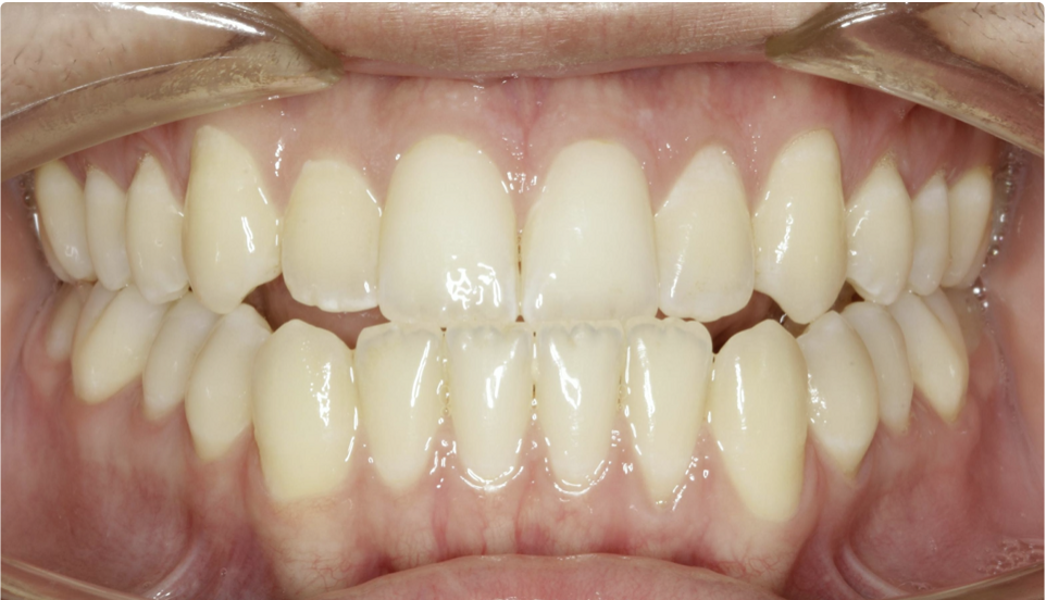

New Age orthodontics and orthopaedics with temporary anchorage devices